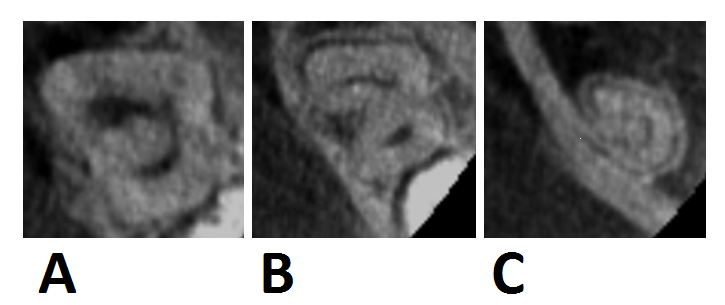

Ryc. 7. Przekroje poprzeczne korzenia drugiego zęba trzonowego żuchwy z kanałem typu C wykonane na różnej wysokości (badanie CBCT). A. w części koronowej korzenia, B. w części środkowej, C. w części wierzchołkowej.